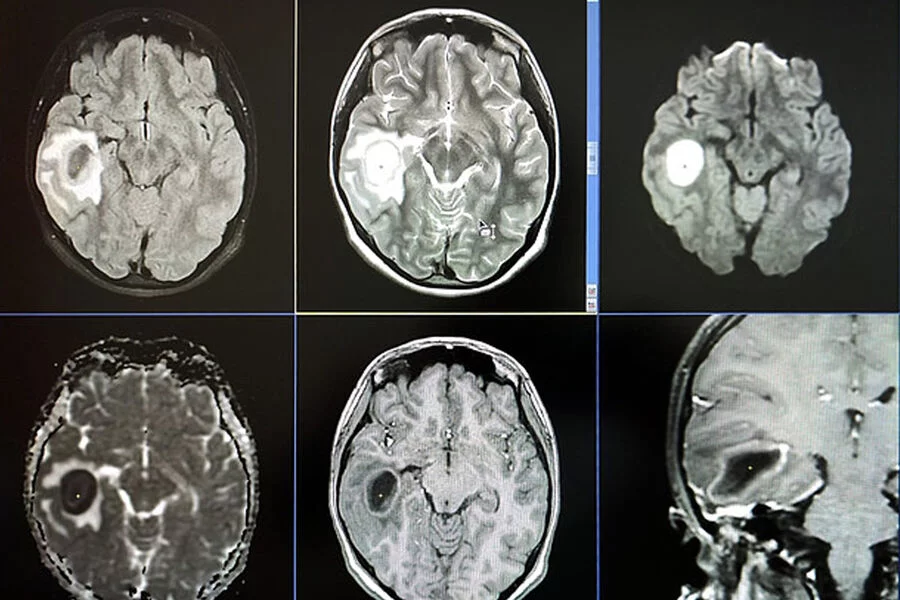

Onun müalicəsi müsbət nəticə vermədiyindən xəstə qıza MRT təyin olunub. Qızın beynində irin aşkar olunub.

Bundan sonra həkimlər qızın üzərində cərrahiyyə əməliyyatı aparıblar və bu əməliyyat zamanı irinli iltihabı aradan qaldırıblar və bununla da uşağın həyatını xilas ediblər.